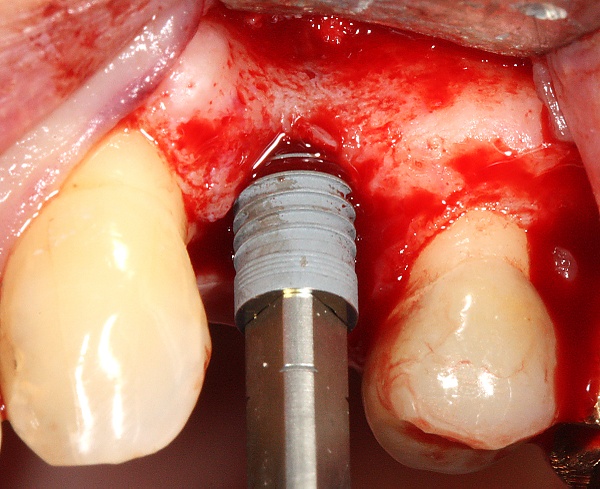

Внутрикостные имплантаты по форме разделяют на корневидные, пластиночные и комбинированные. Наибольшее распространение имеют корневидные имплантаты, которые могут быть цилиндрической или конической формы.

Корневидные имплантаты могут значительно отличаться по макродизайну резьбы: неагрессивная, агрессивная с глубокими полозьями, смешанные.

Следует понимать, что искомым результатом в стоматологии является восстановление функции и эстетики зубо-челюстной системы в целом. Зубной имплантат в этом контексте может быть лишь этапом общего процесса, являясь опорой для финальной реставрации. Имплантат должен быть как функциональным для пациента, так и удобным в работе для стоматолога на этапе установки. Этому способствуют: продуманный хирургический набор фрез и отвёрток; логичный последовательный протокол подготовки остеотомии (костного ложа). Наличие разных форм имплантата даёт возможность имплантологу выбрать оптимальный дизайн в зависимости от костных условий. Например, в пористой, губчатой кости больше подойдет имплантат конусной формы с «агрессивной» самонарезающей резьбой, а достигнуть адекватной стабилизации цилиндрическим имплантатом с мелким шагом резьбы будет трудной задачей. Если требования не удовлетворены, то система имплантатов так или иначе отвергается.

Техника